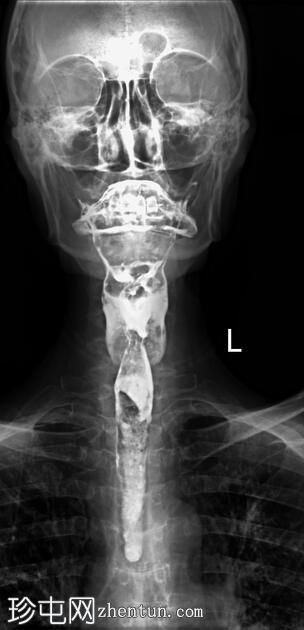

正位

正位和侧位图像显示造影剂在咽部积聚,并伴有钡剂误吸至气道和支气管树。未见

肺

实变。

此外,胸椎存在退行性改变,表现为终板硬化和边缘骨赘形成。

透视图像显示钡剂误吸覆盖喉部和气管支气管树。